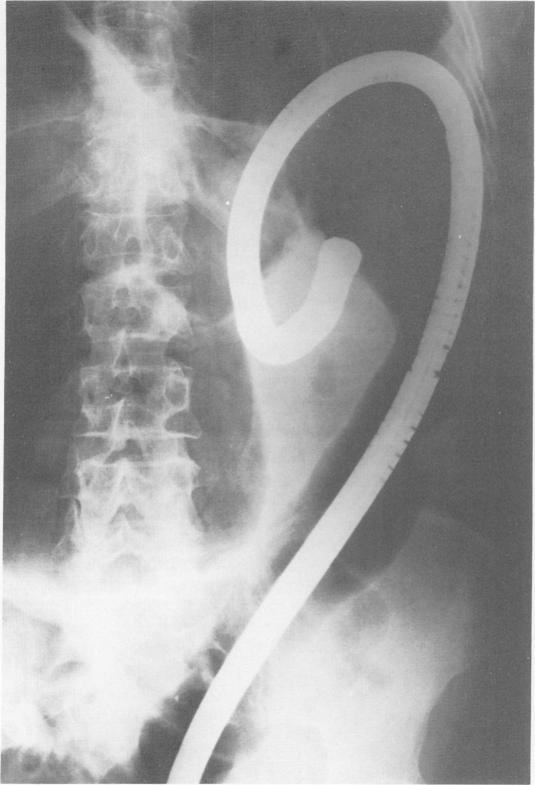

结肠镜检查治疗结肠扭转

Treatment of volvulus of the colon by colonoscopy.

The flexible colonoscope has notable advantages over rigid instruments and can be offered as an alternative and (probably) preferable method for non-surgical reduction of colonic volvulus. When operative intervention is called for because of repeated bouts of sigmoid volvulus, colonoscopy offers a means of preoperative deflation of the twisted loop, allowing time to prepare the bowel and correct systemic disturbances such as electrolyte imbalance. The first successful management of a case of recurrent sigmoid volvulus using fiberoptic flexible colonoscope is presented. It is suggested that the fiberoptic colonoscope may have similar application for instances of volvulus occurring more proximal than in the sigmoid colon. Sigmoid volvulus in children even though rare might also be amenable to correction by colonoscopy.

与硬质器械相比,可弯曲结肠镜具有显著优势,可作为非手术复位结肠扭转的一种替代方法,且可能是更可取的方法。当因乙状结肠扭转反复发作而需要进行手术干预时,结肠镜检查可提供一种使扭转肠袢术前减压的方法,从而有时间准备肠道并纠正诸如电解质失衡等全身紊乱情况。本文介绍了首例使用纤维光学可弯曲结肠镜成功处理复发性乙状结肠扭转病例的情况。有人提出,纤维光学结肠镜对于发生部位比乙状结肠更靠近近端的扭转情况可能有类似的应用价值。儿童乙状结肠扭转尽管罕见,但也可能适合通过结肠镜检查进行矫正。